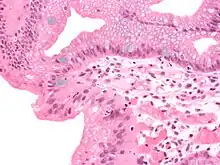

Both macroscopic (from endoscopy) and microscopic positive findings are required to make a diagnosis. Barrett's esophagus is marked by the presence of columnar epithelia in the lower esophagus, replacing the normal squamous cell epithelium—an example of metaplasia. The secretory columnar epithelium may be more able to withstand the erosive action of the gastric secretions; however, this metaplasia confers an increased risk of adenocarcinoma.[15]

Intestinal metaplasia

The presence of goblet cells, called intestinal metaplasia, is necessary to make a diagnosis of Barrett's esophagus. This frequently occurs in the presence of other metaplastic columnar cells, but only the presence of goblet cells is diagnostic. The metaplasia is grossly visible through a gastroscope, but biopsy specimens must be examined under a microscope to determine whether cells are gastric or colonic in nature. Colonic metaplasia is usually identified by finding goblet cells in the epithelium and is necessary for the true diagnosis.